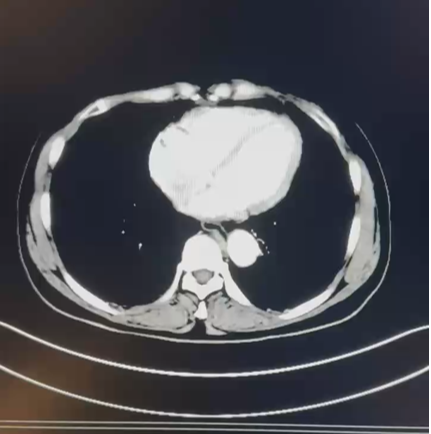

CT:1. 右肾癌伴右肾静脉受累,侧支循环形成;2. 右肾上腺结合部结节灶,转移可能;3. 右输尿管上段管壁局部增厚:侵犯?4. 左肾囊肿。

PETCT:1. 右肾中-下份混合密度软组织肿块,糖代谢轻度升高,SUVmax6.4, 右肾内糖代谢稍增高灶,SUVmax3.8,右肾癌合并肾静脉瘤栓形成;2. 右肾上腺结合部低密度灶,糖代谢轻度增高,转移瘤,SUVmax3.1。

2021.10.14 行腹腔镜下右肾根治性切除术+右肾上腺肿瘤切除术。

术后病理:透明细胞性肾细胞癌,ISUP 分级 G3 级;肿瘤性坏死:20%;肾静脉及腔静脉壁浸润;肾上腺皮脂腺瘤。pT3NxMx